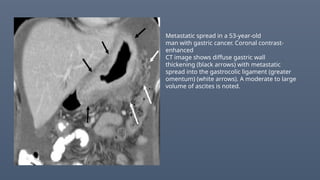

Metastatic spread in a 53-year-old

man with gastric cancer. Coronal contrast-

enhanced

CT image shows diffuse gastric wall

thickening (black arrows) with metastatic

spread into the gastrocolic ligament (greater

omentum) (white arrows). A moderate to large

volume of ascites is noted.

Metastatic spread ina 53-year-old man with gastric cancer. Coronal contrast- enhanced CT image shows diffuse gastric wall thickening (black arrows) with metastatic spread into the gastrocolic ligament (greater omentum) (white arrows). A moderate to large volume of ascites is noted.